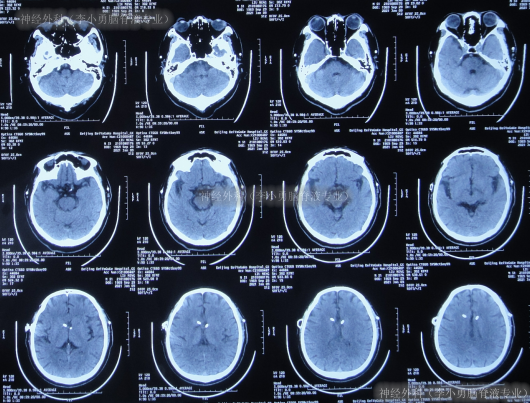

出院后3余年即2020年10月21日,第2次出现行走不稳,头晕;于是第2次就诊给予脑室腹腔分流术的医院,就诊期间出现嗜睡,查头颅CT(图-1)后给予调高分流泵压。

图-1:2020年10月21日头颅CT